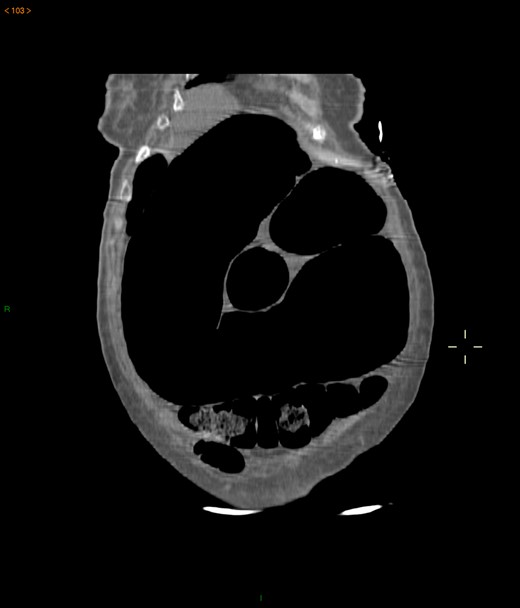

Case 2: A 92-year-old women, without previous abdominal surgery or history of abdominal trauma or peritoneal infections was admitted to the emergency department with generalized abdominal pain. Physical exam revealed markedly distended abdomen with generalized abdominal pain with tenderness. Laboratory investigation on admission: white cell count of 30.200/mm3 with 84.7% neutrophils, protein C reactive of 13.6 mg/dL and lactates of 2.17 mmol/l. Abdominal X-ray showed a marked colonic enlargement. Abdominal-pelvic CT identified a colonic volvulus associated with a transmesocolic hernia with transmural necrosis of the colon sigmoid (Figs 2 and 3). The patient was proposed to laparotomy during which a volvulus of colon sigmoid with transmural necrosis in a strangulated transverse transmesocolic and transomental (great omentum) hernia was identified (Figs 4 and 5). A Hartmann procedure was conducted and the patient was discharged at fifth post-operative day. At 3 months follow-up consultation, the patient remained free of complains.

Abdominal-pelvic CT—transverse plane: colonic volvulus associated with a transmesocolic hernia with transmural necrosis of the colon sigmoid.